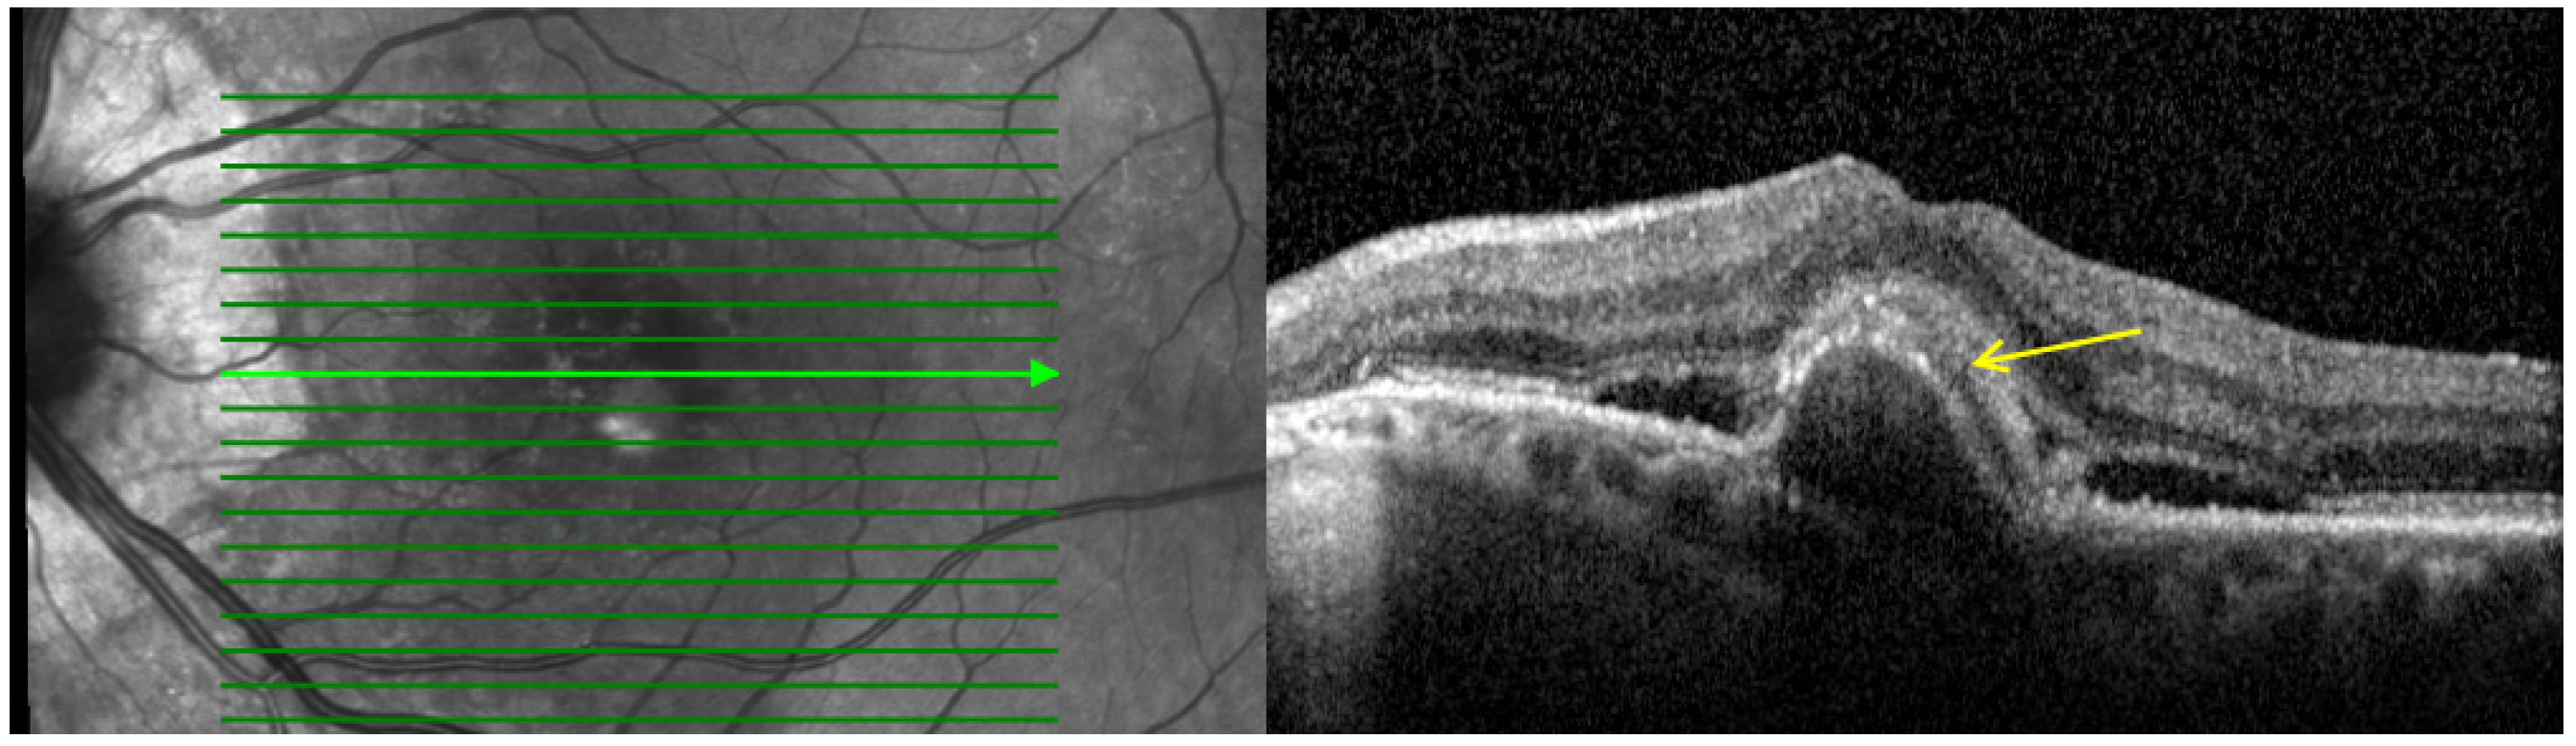

- Hyperreflective dots (HRDs): Defined as small, well-circumscribed lesions with a reflectivity equal to or greater than the RPE as shown in Figure 2. These lesions often occur over drusen and are associated with delays in visual acuity. It is hypothesized that reduced oxygen supply promotes anterior migration of RPE cells, which manifests as HRDs. On the other hand, HRDs in nAMD are also thought to be microglia, common immune cells in the inner retina that migrate from the inner retina to the outer retina when activated in an environment associated with degeneration [27,28].